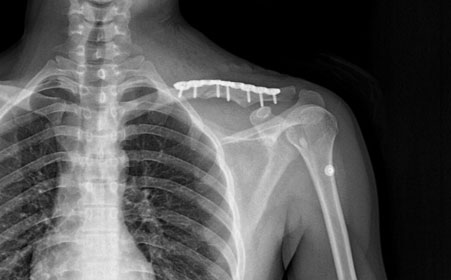

2、肩锁关节脱位是描述肩锁关节中的各种韧带受损的术语。一度损伤:肩锁韧带被拉长;二度扭伤肩锁韧带破裂、喙锁韧带被拉长;三度扭伤:肩锁韧带和喙锁韧带都破裂。

3、锁骨骨折在儿童的骨折中非常常见,经常发生在当肩外侧倒地时或者倒地伸手支撑时。锁骨经常中间断裂。